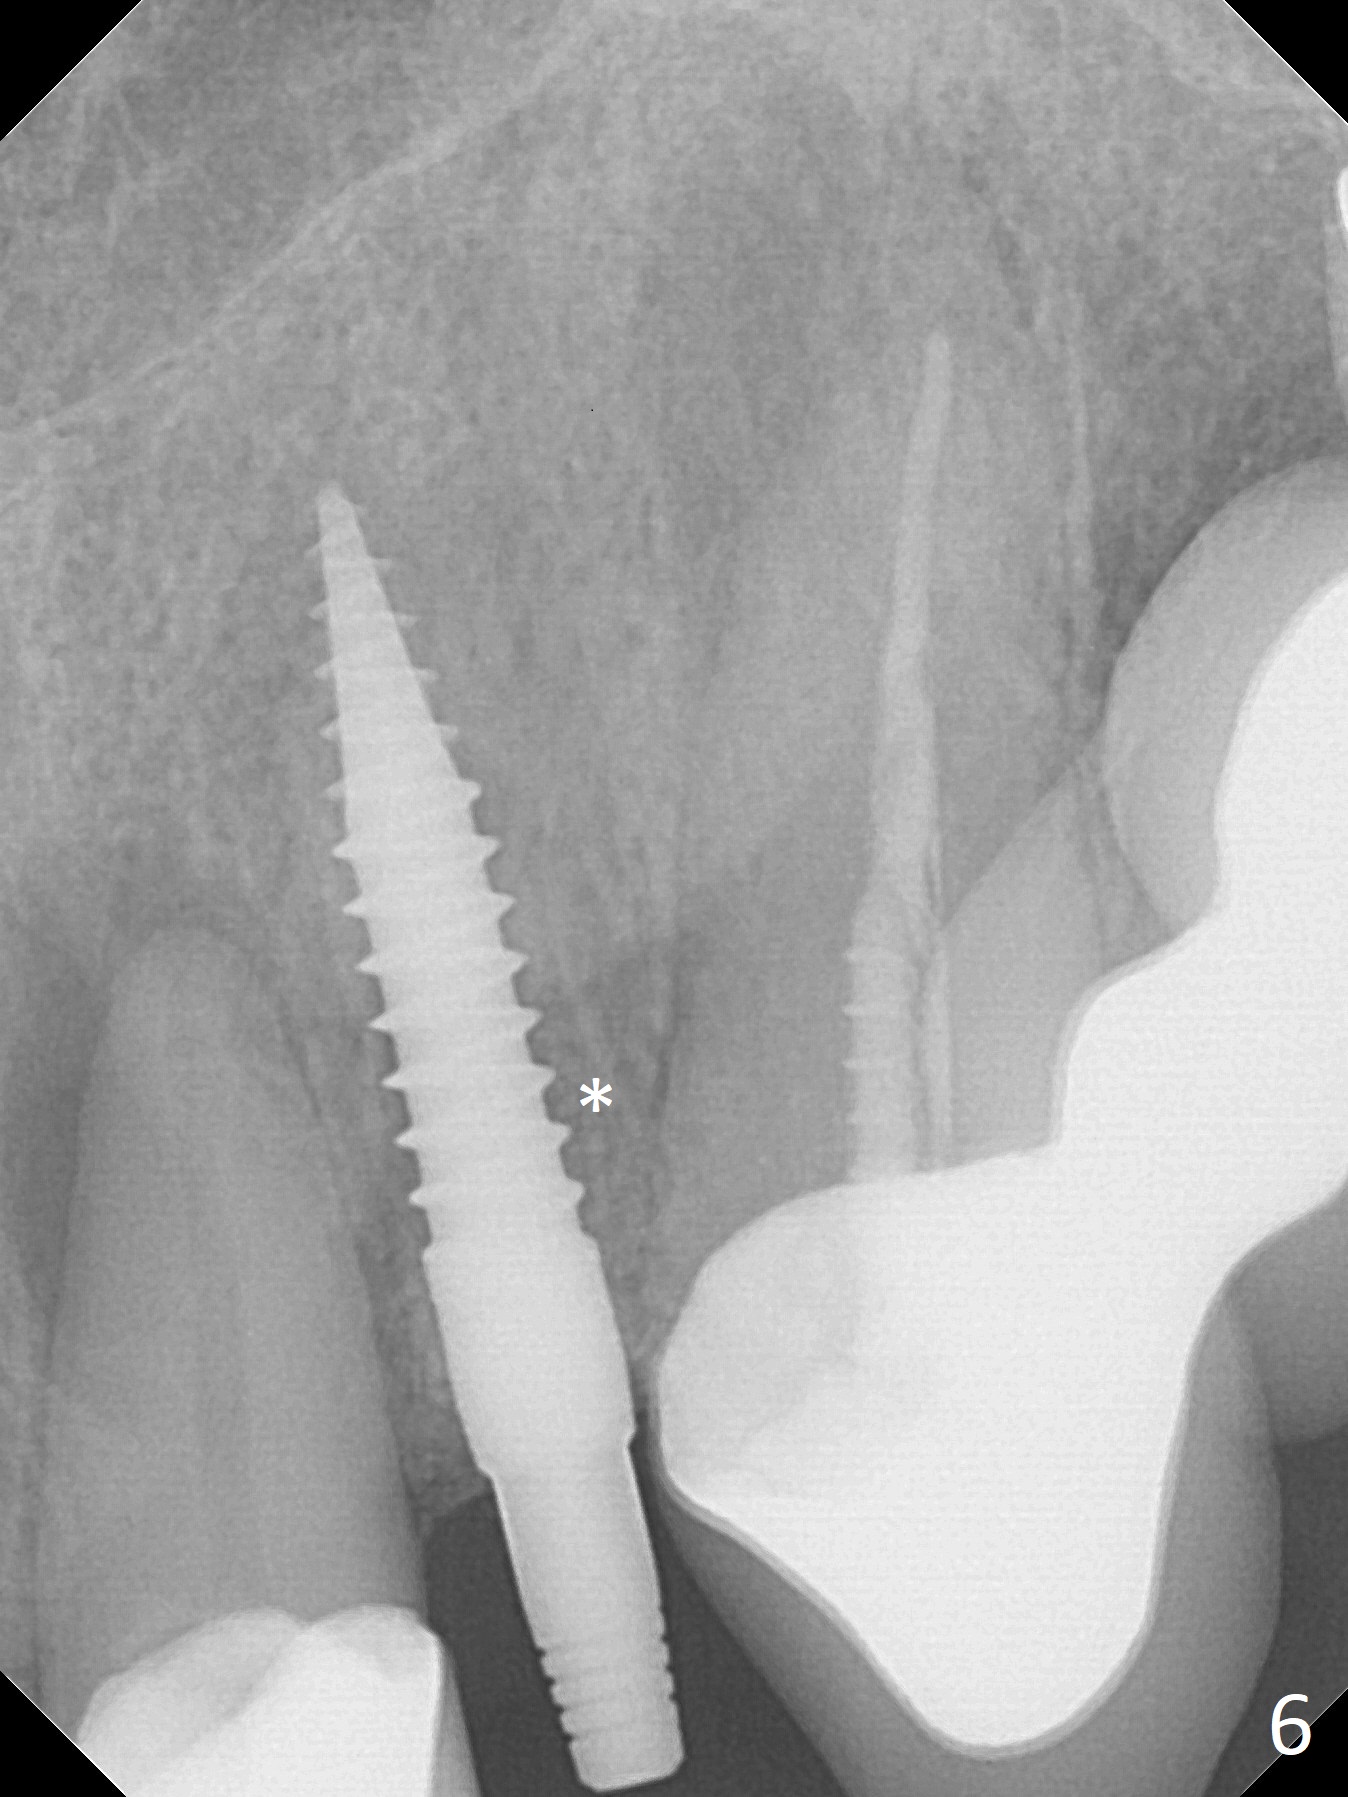

The tooth #10 fractures at the cervix, but is attached to the gingiva.  After extraction of the coronal portion of the tooth, the mesiodistal space palatally is found to be narrow (~4.7 mm, Fig.1).  It appears that a 1-piece implant is indicated because of the narrow mesiodistal space.  In fact the buccal plate of the socket is intact (Fig.2).  The initial osteotomy seems to be mesial (Fig.1) and is moved distal using Lindamann bur.  After sequential osteotomy, a 3x10 mm dummy implant is still mesial (Fig.4).  Following further distalization, a 3x14 mm implant is placed (Fig.5,6; <30 Ncm).  Vera Graft is placed in the remaining socket prior to provisional fabrication (Fig.6 *).  The socket outline disappears 7 months postop (Fig.7).  Panoramic X-ray is taken 1 year 3 month post cementation.